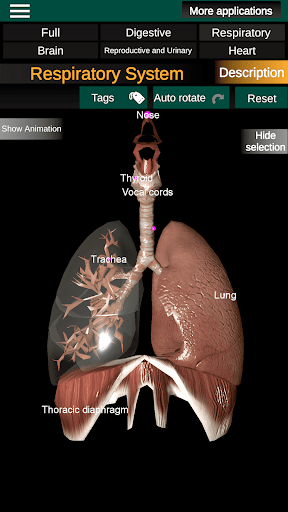

* Sistem pernafasan, yang meliputi trakea, bronkus, paru-paru dan animasi sistem ini.